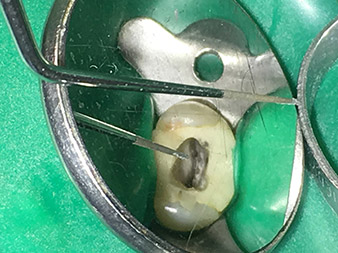

La punta 3E está especialmente concebida para la retirada de limas para endodoncia rotas o partidas. Mi experiencia me ha demostrado que esto es posible en el área coronal hasta la sección central del canal si se dispone de un aumento óptico correspondiente (lupa con un factor de aumento de 3,6 o, mejor, un microscopio).

En este caso debe trabajarse con una punta no diamantada y muy puntiaguda, pues así es posible liberar los fragmentos de instrumentos rotos en el área de la dentina ayudándose de un microscopio. Además, el instrumento también resulta ideal a fin de liberar una lima para canal radicular rota en el área coronal para, a continuación, sacarla mediante vibración utilizando la punta 5E.

Para otras indicaciones de los canales radiculares, deben utilizarse ayudas visuales como una lupa o, mejor aún, un microscopio. Además, considero muy importante que todas las aplicaciones del canal, a excepción de la activación del líquido de enjuague, corra a cargo de colegas especializados que dispongan de los conocimientos técnicos y de la experiencia necesarios en este campo.